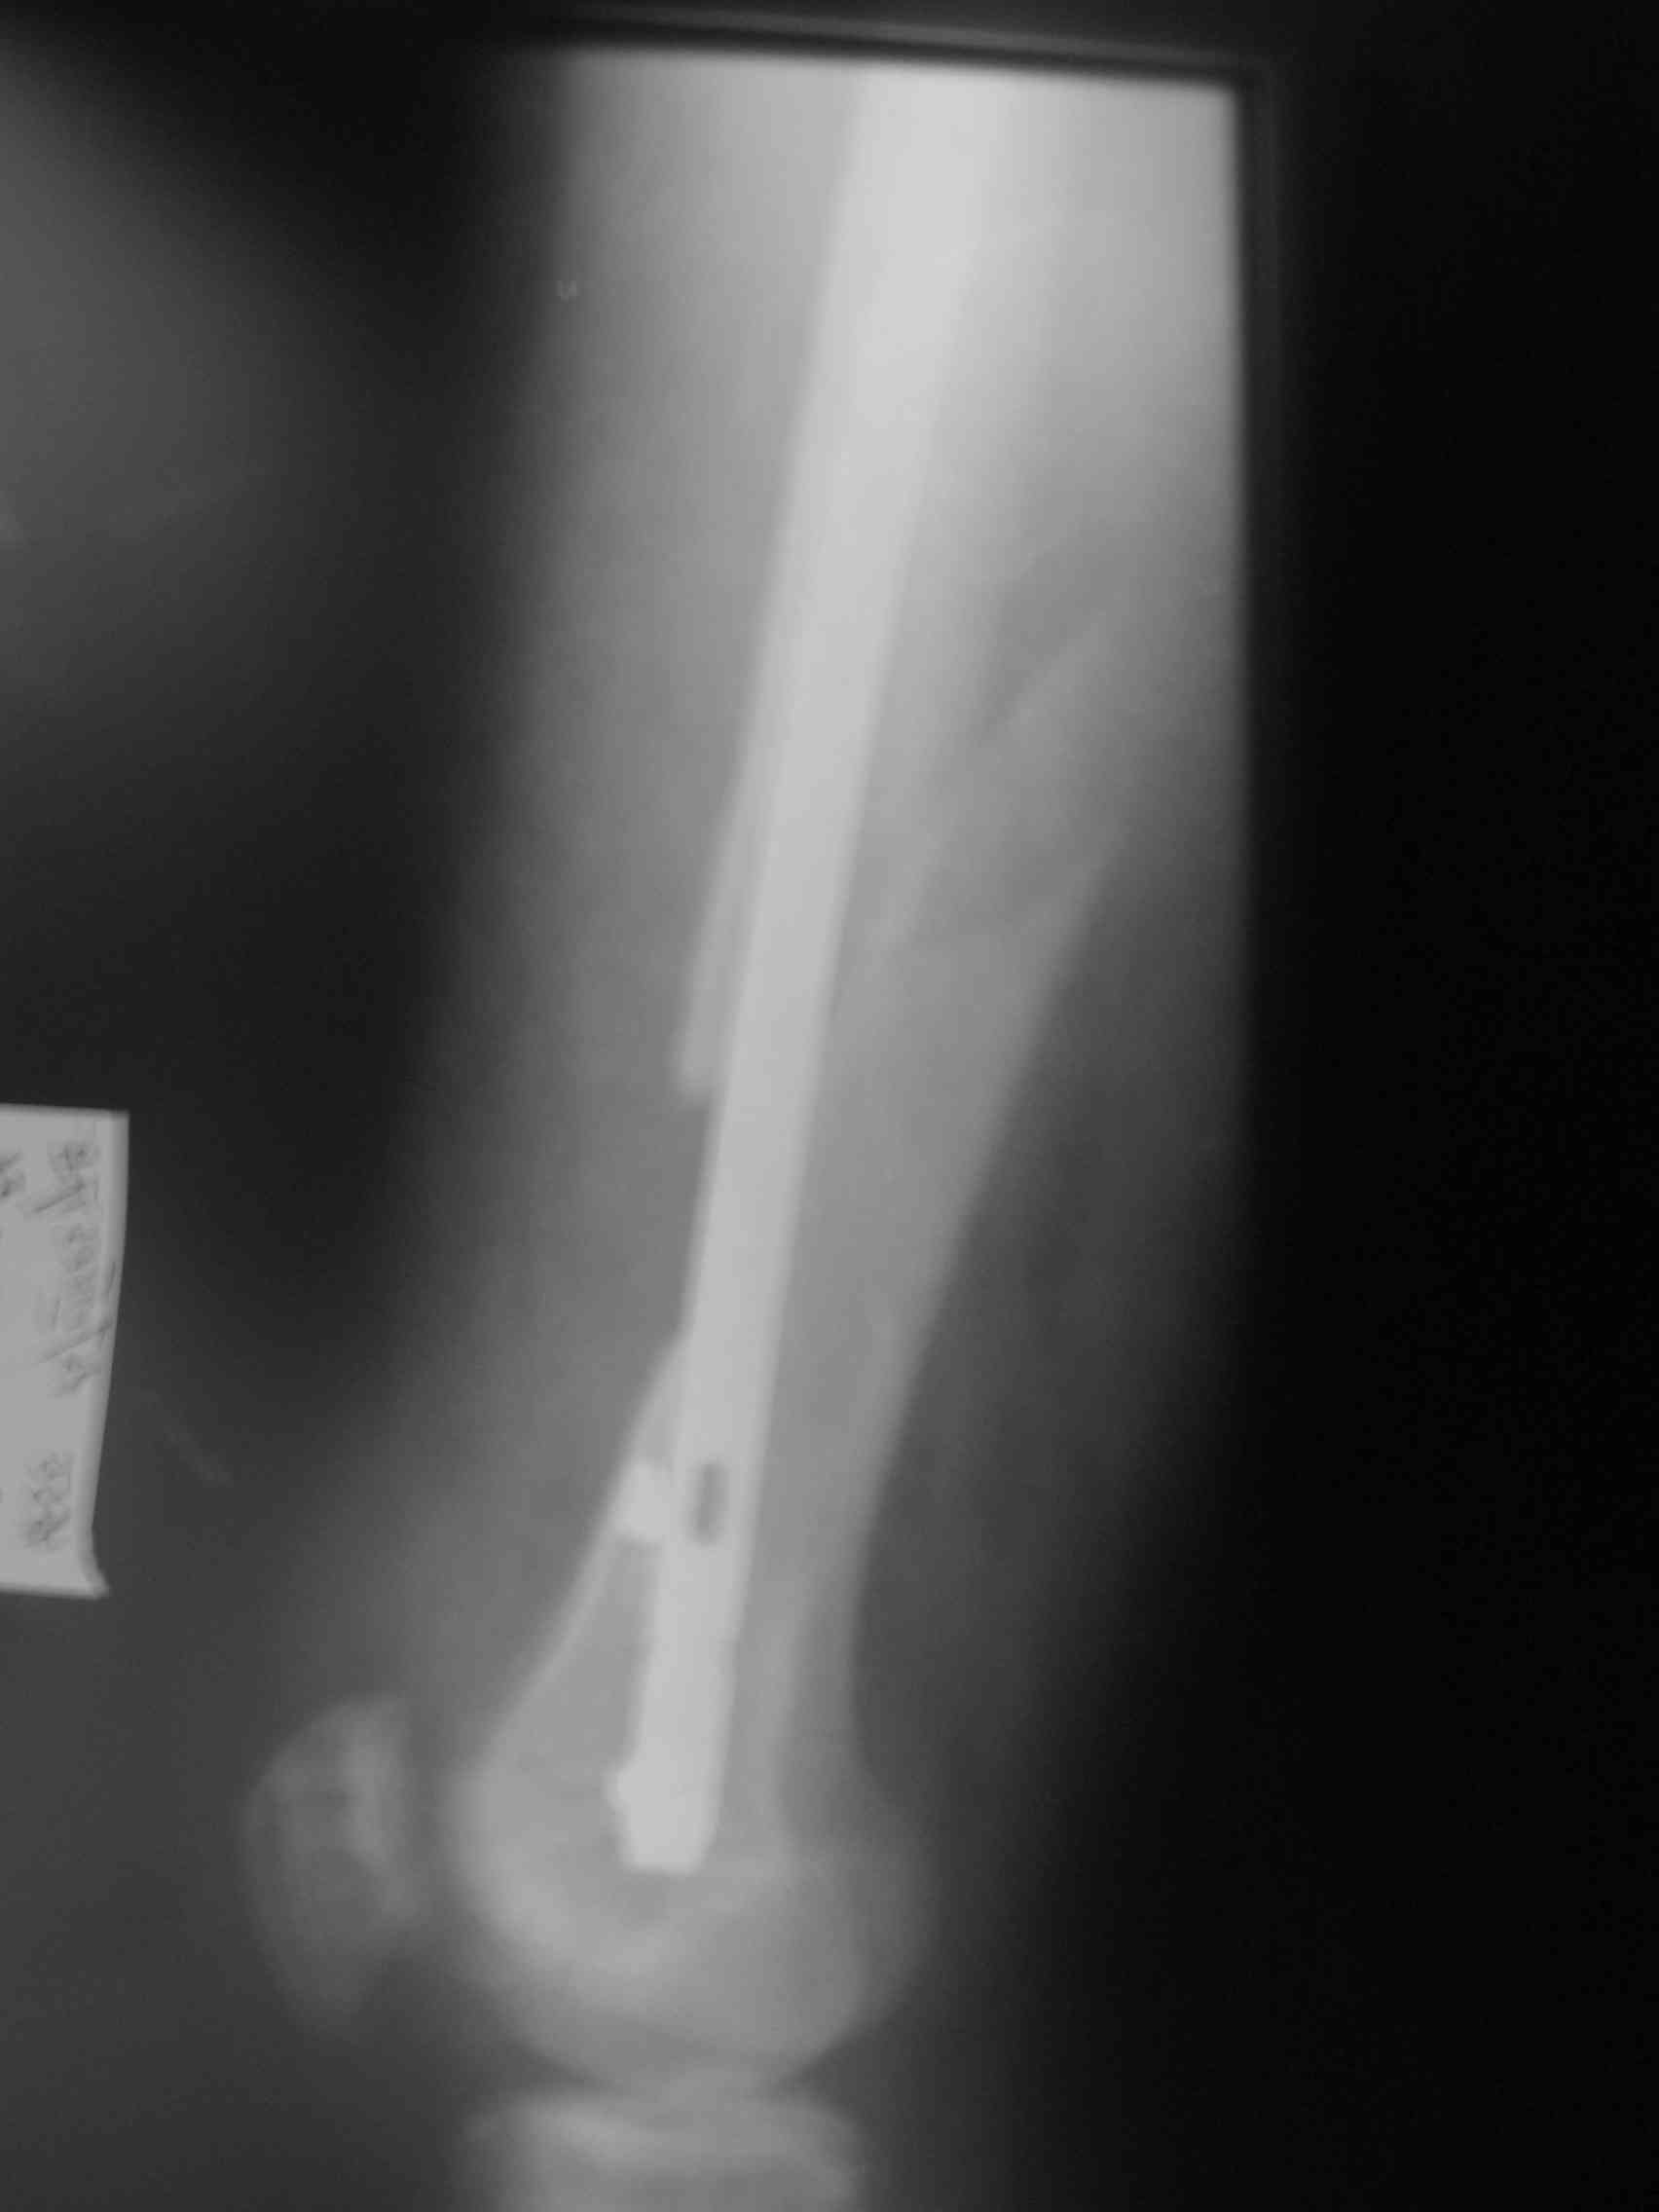

Посылаю первый снимок, который попался по руку.

Саркомные переломы обычно не срастаются, по этому не зависимо от места метастаза фиксатор устанавливается максимально длинный и обязательно с блокировкой что бы сохранять длину кости даже после роста метастаза или при дополнительно метастазировании. В Вашем случае блокировочные гвозди выглядят тонкими и проведены только через один кортекс. Гвоздь толщиной более 10 мм с блокировочными шурупами 4-5 мм проведенные через обе кортикальные пластинки может обеспечить опороспособность даже если перелом не срастется или литический процесс распространится.